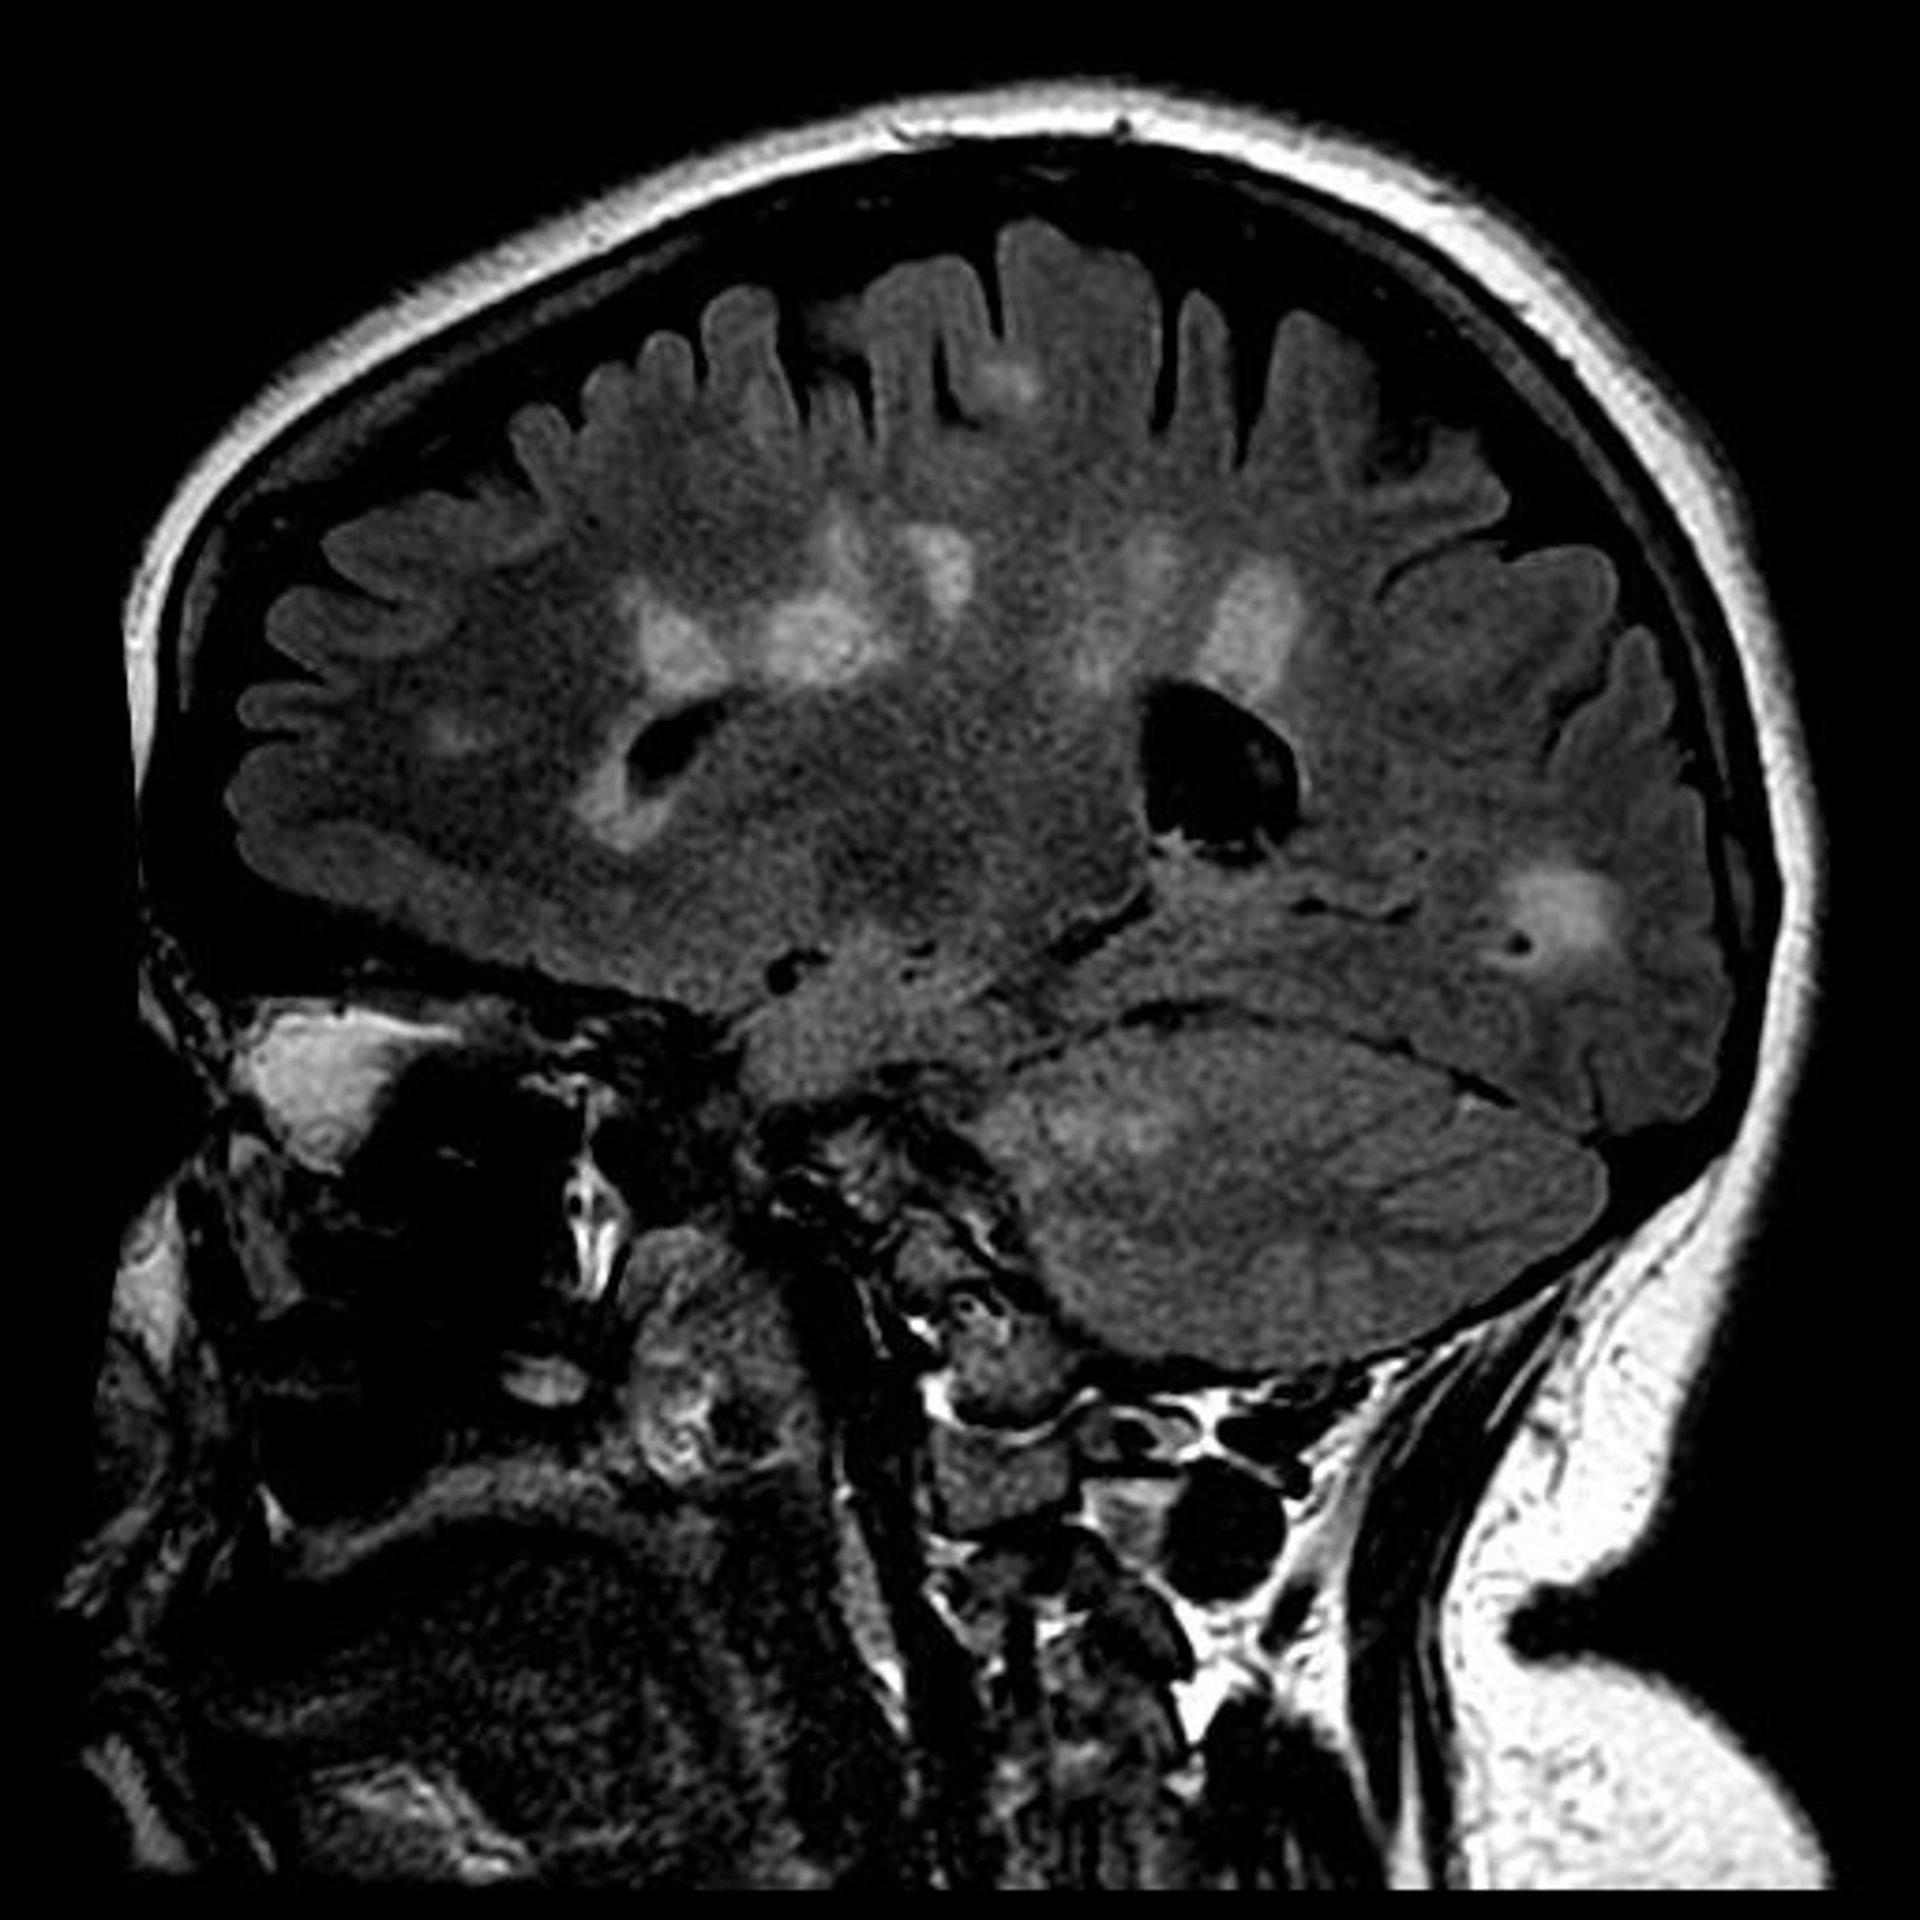

Archivo - Cicatrización del cerebro en la esclerosis múltiple

Archivo - Cicatrización del cerebro en la esclerosis múltiple - UNIVERSITY OF BRITISH COLUMBIA - Archivo